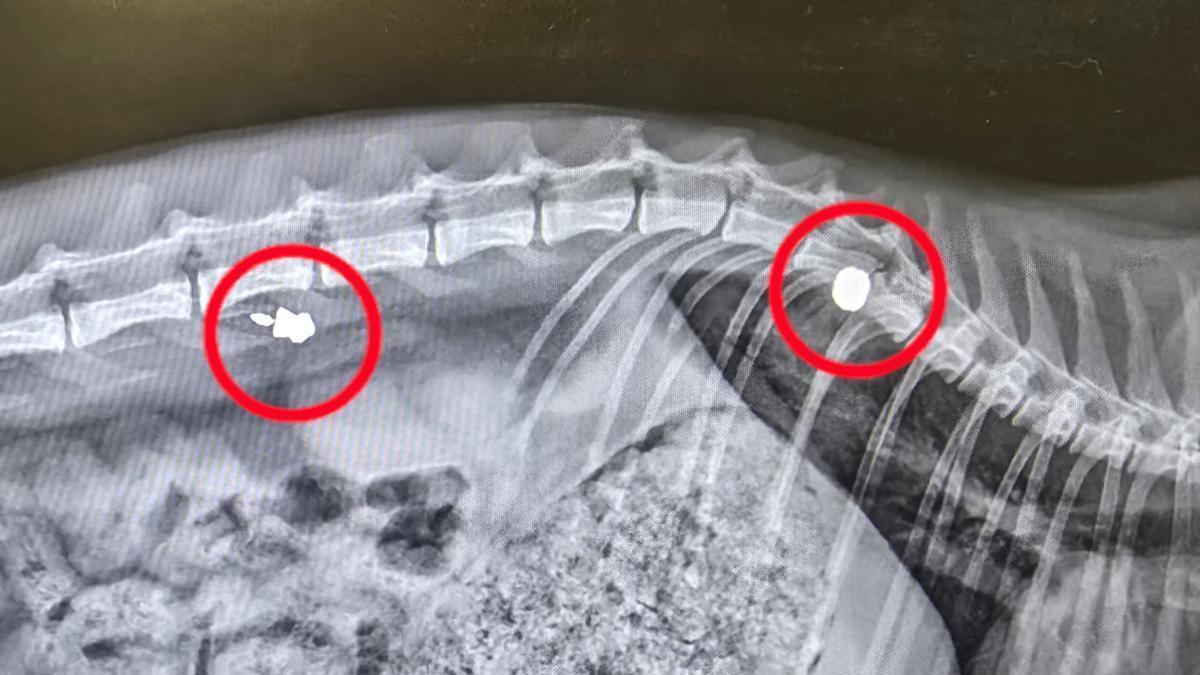

La Guardia Civil de Sant Joan d'Alacant investiga la agresión a una gata que recibió disparos de perdigón en una calle del municipio y uno de los balines se le quedó alojado dentro, junto a la columna vertebral. La gata ha quedado inicialmente afectada por una paraplejia y tenía dos perdigones dentro del cuerpo, aunque uno de los dos balines corresponde a un disparo más antiguo.

El felino está ingresado desde el sábado en una clínica veterinaria del Cabo de la Huerta en Alicante, donde ha sido intervenida este martes con la intención de extraerle los dos proyectiles que tiene alojados dentro de su cuerpo.

Una gata apareció en la vía pública con dos disparos efectuados con una escopeta de aire comprimido, aunque el examen posterior realizado en la clínica veterinaria determinó que presentaba una herida reciente y otra anterior.

La presidenta de SOS Ayuda Animal auxilió a la gata y tras recogerla la trasladó a una clínica veterinaria en el Cabo de las Huertas. Allí le hicieron una radiografía y comprobaron que presentaba dos proyectiles alojados en su cuerpo, uno de ellos antiguo.

En la denuncia presentada el domingo ante la Guardia Civil, la presidenta de SOS Ayuda Animal indica que corre peligro la vida de la gata herida y que si sobrevive quedará paralítica. No obstante, la operación realizada este martes ha confirmado que la médula no estaba rota, pero tiene una contusión y no se sabe si recuperará la movilidad una vez baje la inflamación.